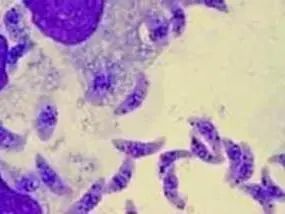

引起的人和动物的感染。弓形虫属于形体最小、结构简单的一类叫作原虫的寄生虫。

猫和其他猫科动物是弓形虫的终宿主,它寄生在这些动物的小肠上皮细胞内,形成囊合子随粪便排出,其他哺乳动物和鸟吃进去发生感染,在它们身体的组织内发育成为包囊。